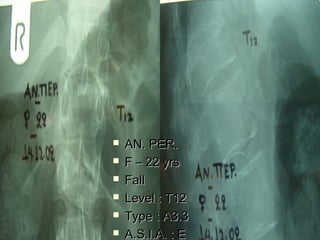

 AANN.. PPEERR..

 FF –– 2222 yyrrss

 FFaallll

 LLeevveell :: TT1122

 TTyyppee :: AA33..33

 AA..SS..II..AA.. :: EE